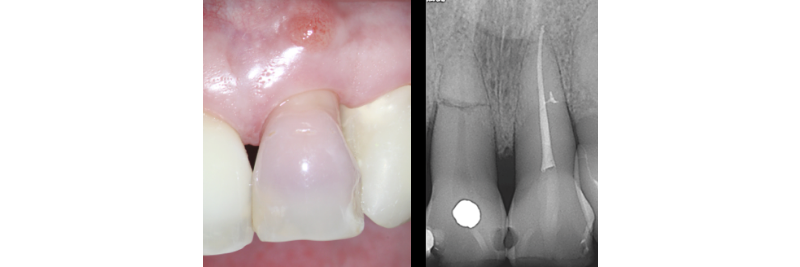

One of the most challenging clinical situations encountered in practice is restoring a “dark tooth” in the esthetic zone (Figs. 1A, 1B).

One treatment option that is often overlooked is internal non-vital tooth bleaching. This can be an excellent treatment option if the tooth has had RCT or needs RCT (Figs. 2A, 2B).